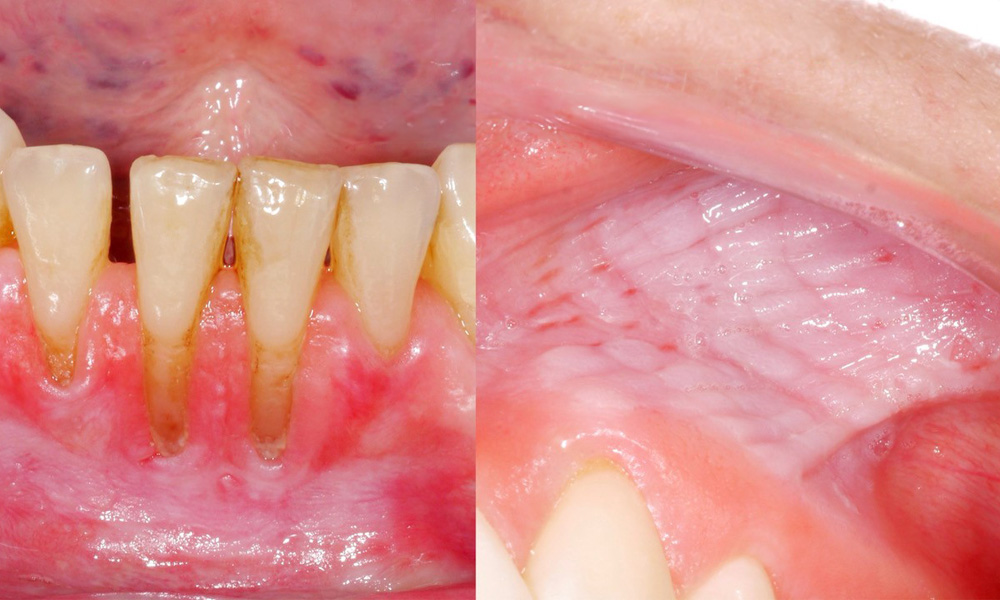

The clinical examination showed that regular consumption of snus can have the following effects on the oral mucosa:

• Approximately 80% of those examined who consumed snus daily had snus-induced mucosal lesions.

• For each additional tin of snus consumed per month, the risk of a more severe mucosal lesion increased significantly.

• Approximately 20% of those examined who consumed snus daily had snus-induced gingival recession.

• For each additional year that snus was consumed, the risk of snus-induced gingival recession increased significantly.